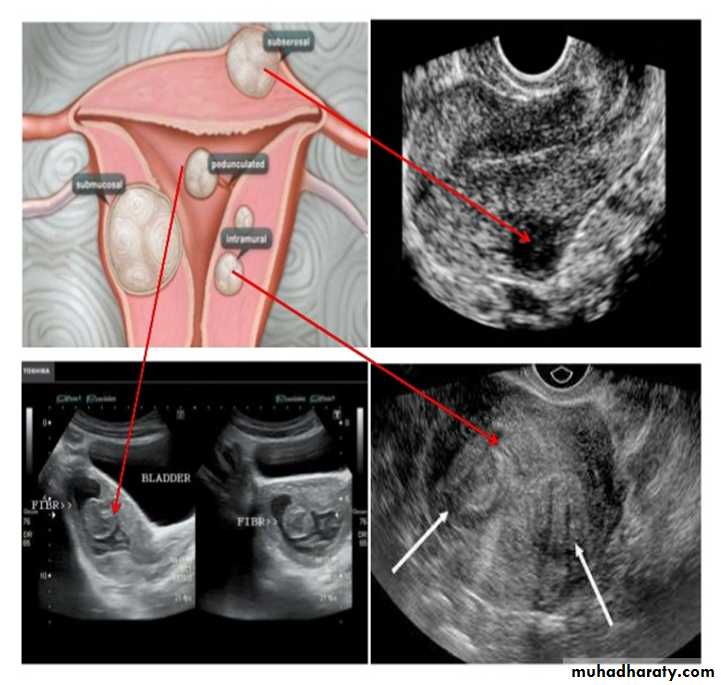

UUUUUUs of pelvic organs :

Ovarian cysts :

Ovarian cysts are commonly encountered in gynecological imaging, and vary widely in etiology, from physiologic, to complex benign, to neoplastic.

Small cystic ovarian structures should be considered normal ovarian follicles unless the patient is pre-pubertal, post-menopausal, pregnant, or the mean diameter is >3.0 cm

Radiographic features

Ultrasound is usually the first imaging modality for assessment of ovarian lesions. Simple ovarian follicular cysts are:

anechoic

intraovarian or exophytic;

have an imperceptible wall